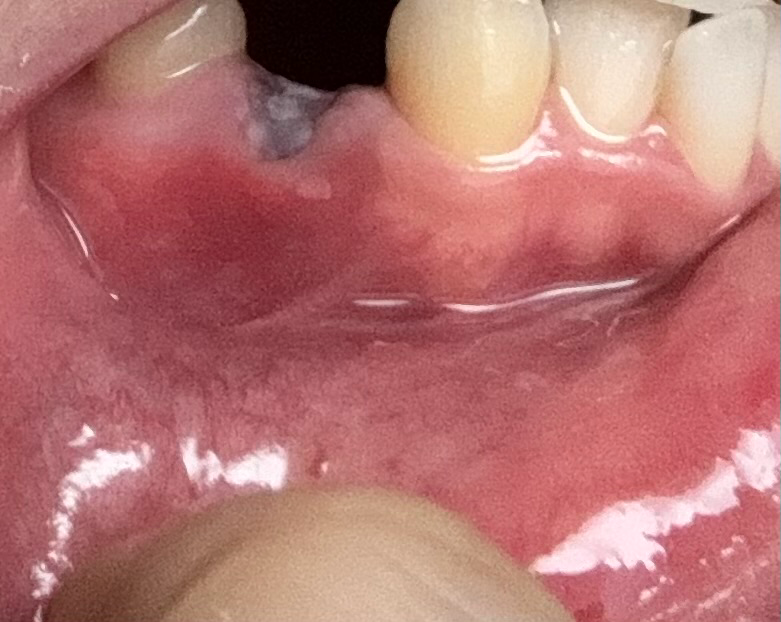

발치한지 3일정도 지났는데 잇몸이 빨개지고 부었어요. 왜 그런 걸까요?

발치한곳 바로 아래가 빨개지고 부었는데 혹시 문제가 생긴 걸까요? 사진보다 더 빨개요

어제까지만 해도 부은 느낌도 없고 괜찮았는데 오늘 저녁부터 계속 거슬리길래 보니까 빨개지고 조금 부었네요..

발치한 부분이 아프진 않은데 무슨 문제가 있는 건가요?

사진상으로는 크게 문제가 잇어 보이는게 없습니다. 발치를 하게되면 아직 상처가 다 아물지 않아서 발적된 상태로 보일수 잇습니다.

발치를 하고 나서 3일 정도 지났다면 지금 사진에서 보는 것과 비슷하게 보입니다. 현재 사진으로는 전혀 감염의 증상은 없으며 시간이 지나면서 잇몸 및 뼈가 회복될 것으로 보입니다. 처방받은 약을 드시고 경과를 지켜보시길 바랍니다.